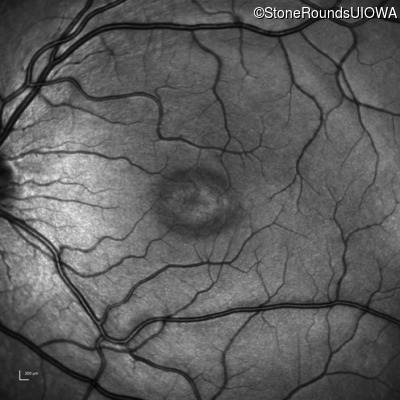

This 6 year old boy first experienced difficulty reading and seeing the blackboard at age 5.

| Age at visit: 6 years |